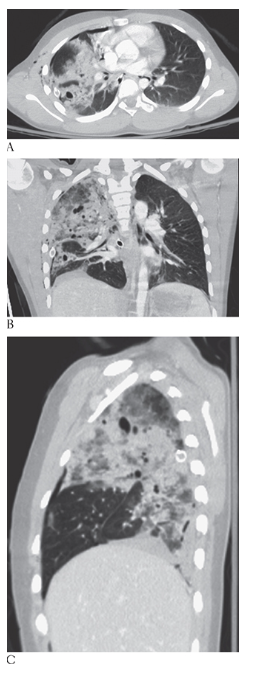

What is A

Superior Vena Cava Syndrome. CECT coronal and MPR CECT sagittal

What is B

Superior Vena Cava Syndrome. CECT coronal images show significant narrowing of the superior vena cava with development of multiple collaterals.

Superior Vena Cava Syndrome. Axial CECT shows significant narrowing of the superior vena cava with development of multiple collaterals.